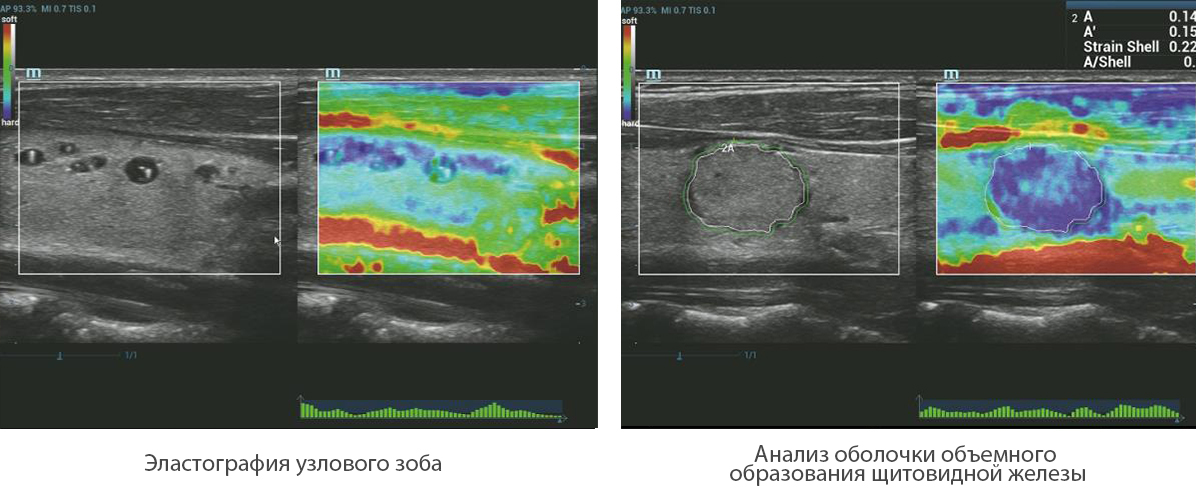

–Ь–µ—В–Њ–і —Н–ї–∞—Б—В–Њ–≥—А–∞—Д–Є–Є Natural Touch

Natural Touch –Њ–±–µ—Б–њ–µ—З–Є—В—М –љ–µ–њ—А–µ–≤–Ј–Њ–є–і–µ–љ–љ—Г—О —З—Г–≤—Б—В–≤–Є—В–µ–ї—М–љ–Њ—Б—В—М –Є –Њ—В–ї–Є—З–љ—Г—О –≤–Њ—Б–њ—А–Њ–Є–Ј–≤–Њ–і–Є–Љ–Њ—Б—В—М —А–µ–Ј—Г–ї—М—В–∞—В–Њ–≤ –≤–љ–µ –Ј–∞–≤–Є—Б–Є–Љ–Њ—Б—В–Є –Њ—В –љ–∞–≤—Л–Ї–Њ–≤ –Њ–њ–µ—А–∞—В–Њ—А–∞, –њ–Њ–≤—Л—И–∞–µ—В –Ї–ї–Є–љ–Є—З–µ—Б–Ї—Г—О –Ј–љ–∞—З–Є–Љ–Њ—Б—В—М –Љ–µ—В–Њ–і–∞ –Є —А–∞—Б—И–Є—А—П–µ—В –≤–Њ–Ј–Љ–Њ–ґ–љ–Њ—Б—В–Є –µ–≥–Њ –њ—А–Є–Љ–µ–љ–µ–љ–Є—П. –£–љ–Є–Ї–∞–ї—М–љ—Л–є –∞–љ–∞–ї–Є–Ј –Ј–Њ–љ—Л –Њ–±–Њ–і–Ї–∞ вАФ –Є—Б–Ї–ї—О—З–Є—В–µ–ї—М–љ–Њ –њ–Њ–ї–µ–Ј–љ—Л–є –Є–љ—Б—В—А—Г–Љ–µ–љ—В –і–ї—П –Њ—Ж–µ–љ–Ї–Є –і–Њ–±—А–Њ–Ї–∞—З–µ—Б—В–≤–µ–љ–љ—Л—Е –Є –Ј–ї–Њ–Ї–∞—З–µ—Б—В–≤–µ–љ–љ—Л—Е –Њ–±—А–∞–Ј–Њ–≤–∞–љ–Є–євАФ –њ—А–µ–і–Њ—Б—В–∞–≤–ї—П–µ—В –і–∞–љ–љ—Л–µ –Њ –Ї–Њ—Н—Д—Д–Є—Ж–Є–µ–љ—В–µ –і–µ—Д–Њ—А–Љ–∞—Ж–Є–Є –Љ–µ–ґ–і—Г –Њ–Ї—А—Г–ґ–∞—О—Й–µ–є —В–Ї–∞–љ—М—О –Є –њ–Њ—А–∞–ґ–µ–љ–љ—Л–Љ —Г—З–∞—Б—В–Ї–Њ–Љ, —З—В–Њ –њ–Њ–Ј–≤–Њ–ї—П–µ—В –Њ—Ж–µ–љ–Є—В—М —Б—В–µ–њ–µ–љ—М –Є–љ—Д–Є–ї—М—В—А–∞—Ж–Є–Є —А–∞–Ї–Њ–≤—Л—Е –Ї–ї–µ—В–Њ–Ї –≤ –Њ–Ї—А—Г–ґ–∞—О—Й–Є–µ –Њ–њ—Г—Е–Њ–ї—М —В–Ї–∞–љ–Є.